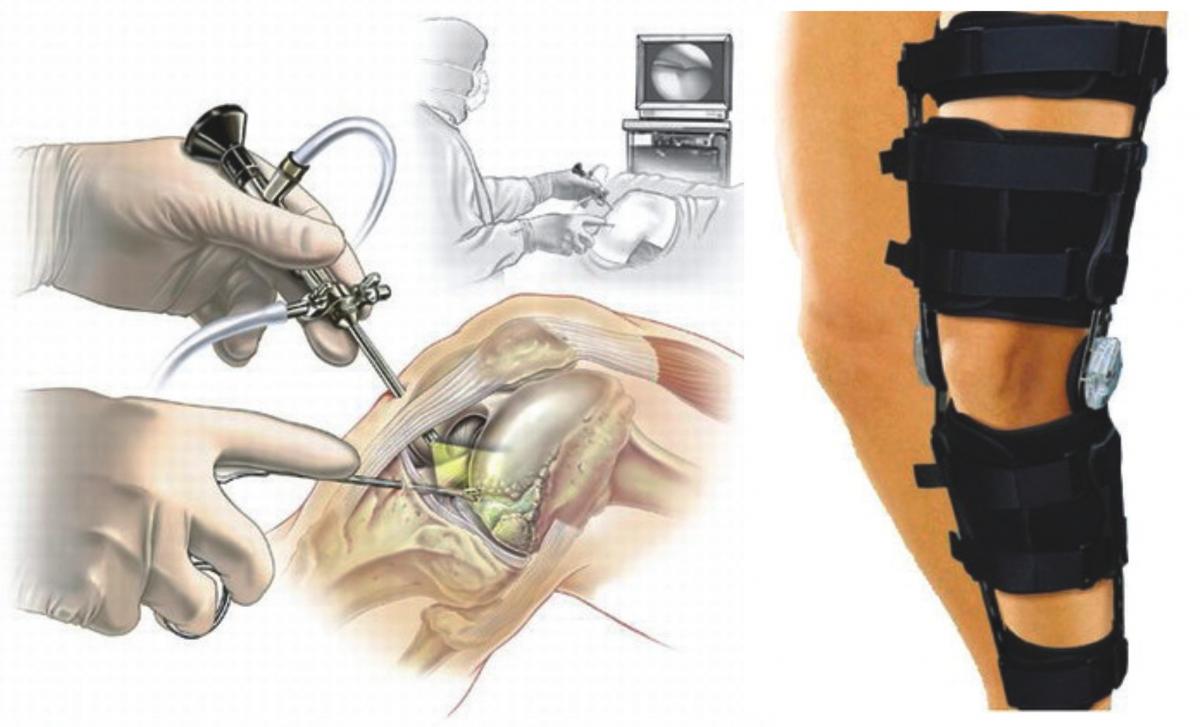

Melhora da mobilidade e da flexibilidade — menos rigidez ao levantar, se curvar ou girar o tronco.

Porque ele não trata apenas o sintoma (a dor) — ele ataca a raiz da questão: desgaste da cartilagem, inflamação articular, comprometimento da estrutura que sustenta a coluna. Em vez de usar apenas analgésicos ou anti-inflamatórios que mascaram o problema, o Maxxi-Art 2.0 trabalha para regenerar, apoiar, fortalecer. Isso faz diferença sobretudo na coluna: quando suas articulações estão bem, a coluna inteira “respira” melhor — menos dor, mais movimento, mais liberdade.